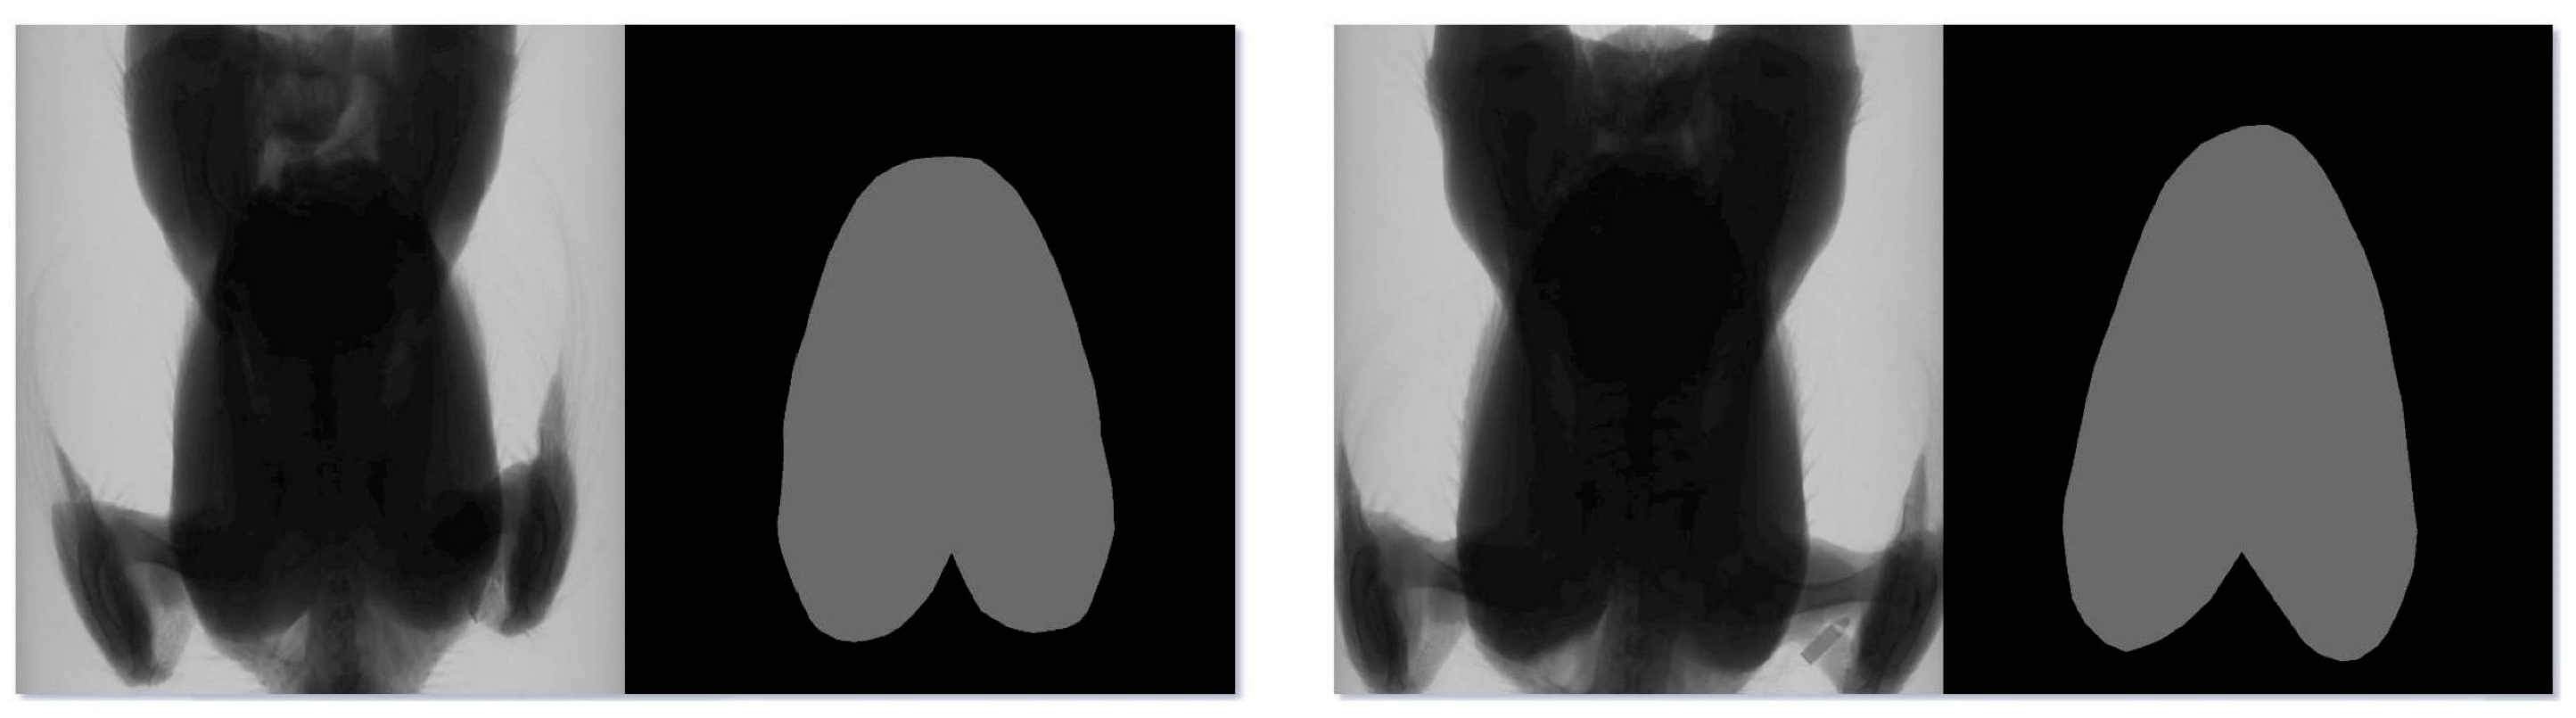

2.3. Data Preprocessing

2.4. MAEFNet Segmentation Model